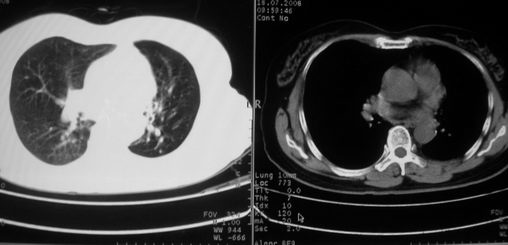

以下是引用李衡钧在2008-7-24 14:24:00的发言:[br]左侧胸廓变小,左肺上叶见大面积致密阴影,其内有空洞及不规则钙化。上纵隔略向左移位,上肺胸膜增厚。左肺门及纵隔淋巴结增大。右肺见散在的致密结节影。[br]印象:继发性肺结核。